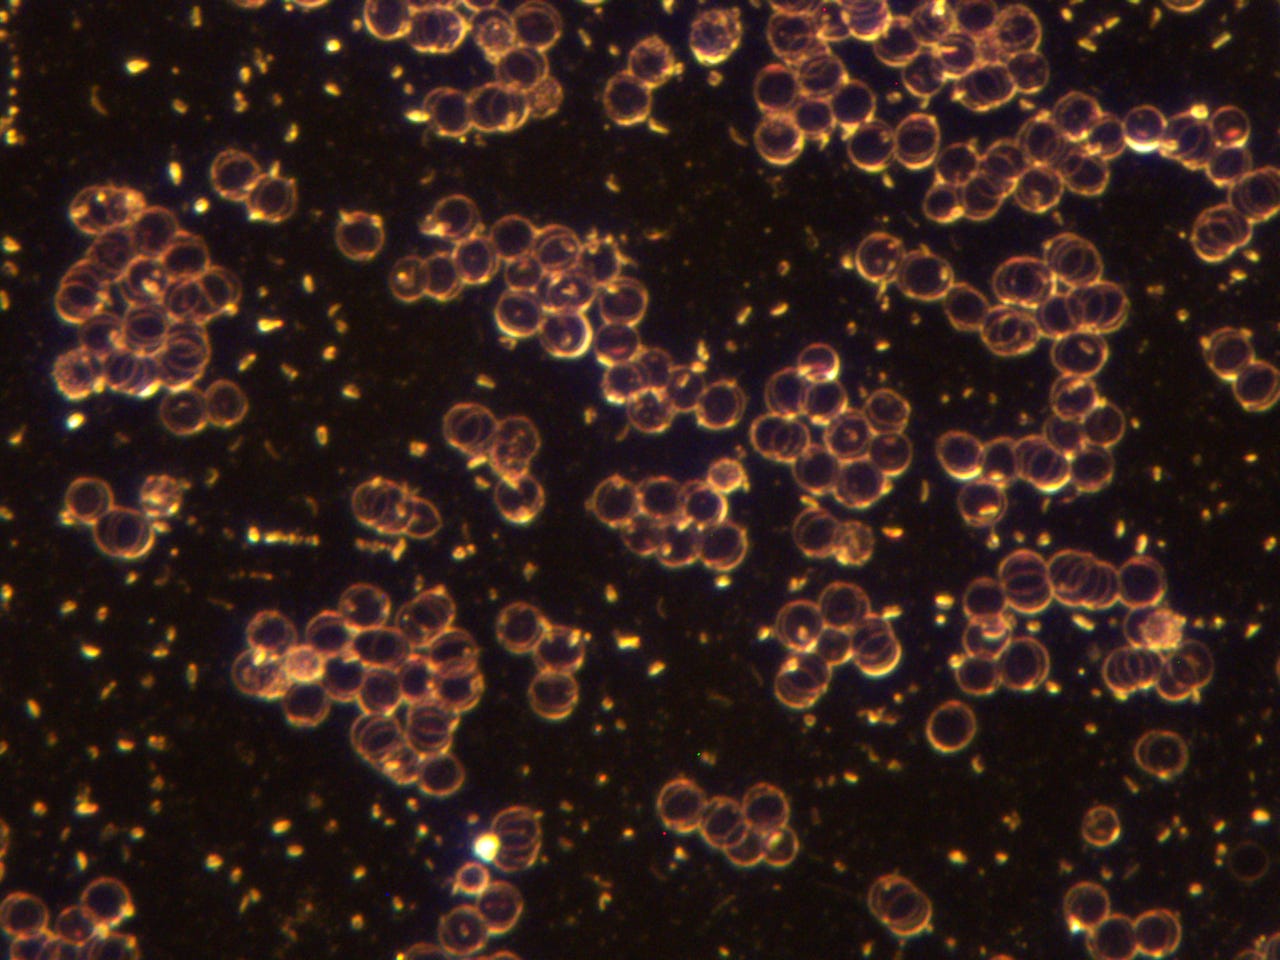

subscribed. Thank you so much. He asked to see my blood before the frequency treatments. The photo’s posted in the previous posts, especially the ones that showed the quantum dots in my blood after the MAH (Major Auto Hemotherapy) with ozone was before the frequency treatments. I am posting them here again, however, I will post some prior to that also.Quantum dots in my blood from Heparin pharmaceutical:

This was the morning after all the quantum dots destroyed my blood:

Anyway here are more before pictures;

I think these really show how messed up my blood was prior to the frequency treatments. I will always be grateful to